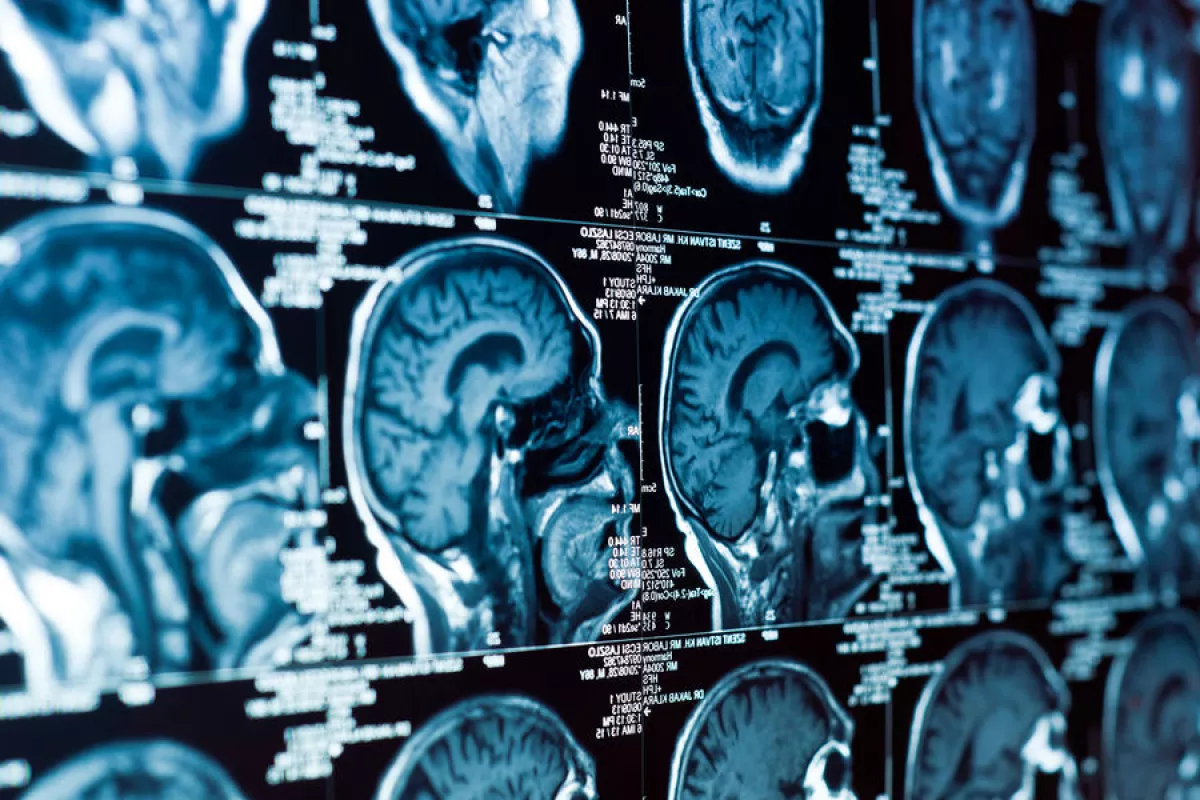

Анализ более 2600 МРТ-сканов мозга людей в возрасте от 30 до 97 лет позволил ученым проследить, как мозг трансформируется с возрастом, и как это соотносится с результатами когнитивных тестов. Выяснилось, что изменения формы мозга происходят неравномерно: одни области сжимаются, другие - расширяются, и у людей с признаками когнитивного снижения эти искажения выражены сильнее.